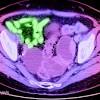

First immunotherapy success for triple-negative breast cancer There is new hope for people with an aggressive type of breast cancer, as an immunotherapy trial shows for the first time that lives can be extended in people with triple-negative breast cancer.

Immunotherapy-chemo combo extends life for women with aggressive form of breast cancer, study finds It's good news for women with triple-negative breast cancer, an aggressive and hard-to-treat form of breast cancer that targets women under 50.